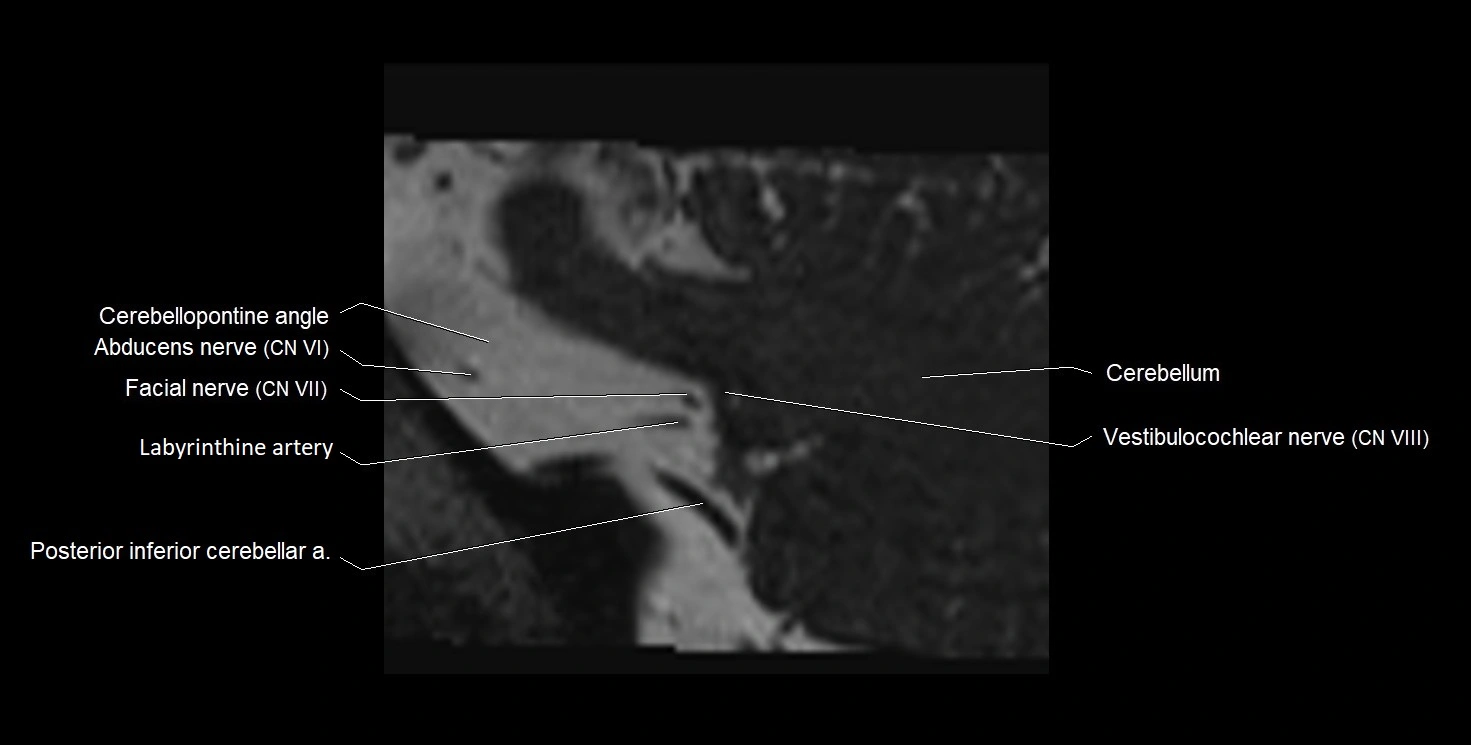

MRI Appearance

• The abducens nerve is a small, thin, linear structure

• Best visualized on high-resolution T2-weighted 3D MRI sequences (e.g., FIESTA or CISS)

• Seen as a hypointense (dark) line running from the brainstem at the pontomedullary junction, traversing the prepontine cistern, and entering Dorello’s canal under the petrosphenoidal ligament, then into the cavernous sinus, and finally the orbit

• May be challenging to visualize in standard MRI due to its small size

• Pathology may be inferred by absence, displacement, or enhancement of the nerve